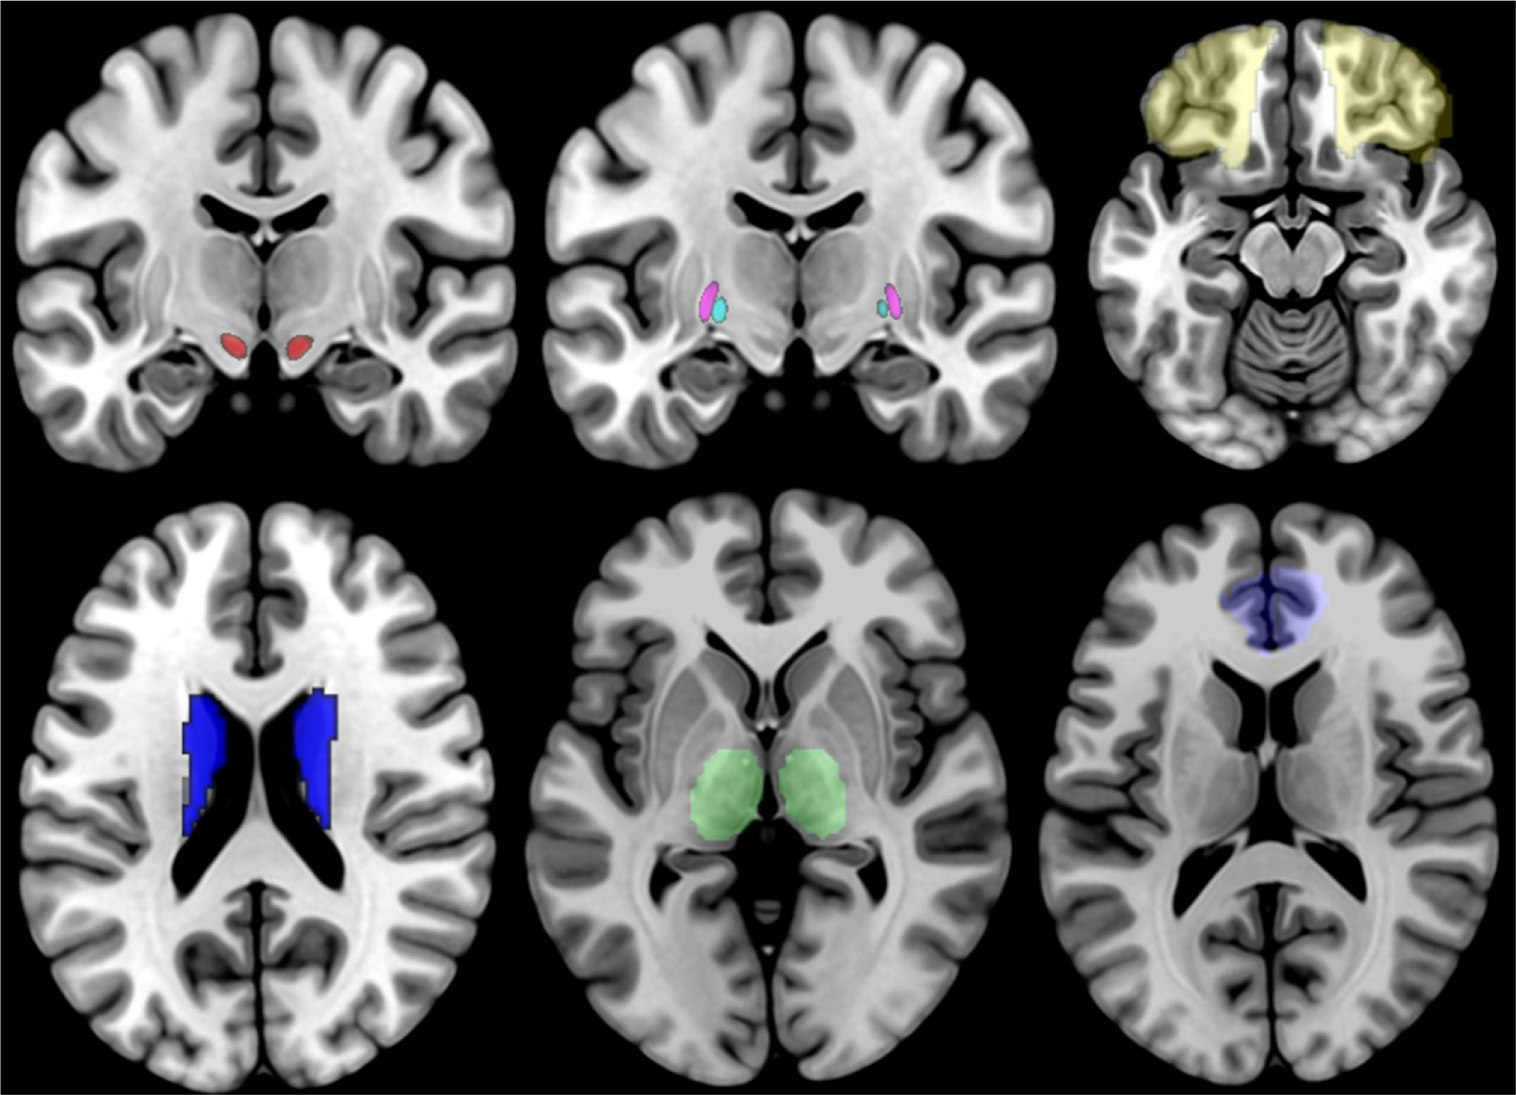

For our analyses, we selected 7 bilateral seeds, for a total of 14 seeds, which correspond to the structures that are part of the direct and indirect CSTC loop (21). These ROIs are the OFC, the ACC, the striatum, the STN, the internal and external globus pallidus (GPi and GPe, respectively), and the thalamus (see Figure 1). The GP and STN ROIs were selected among the ROIs provided by the 7T ATAG atlas of Basal Ganglia, while all the other seeds corresponded to the ROIs provided by the AAL2 atlas. For the ROI-to-ROI analysis, we looked at bidirectional FC results and considered significant only those regions that survived at a peak level threshold of p < 0.05 corrected for multiple comparisons [false discovery rate (FDR)] in both directions.

Figure 1

Illustration of the 14 ROIs, with the STN shown in red, the GPi shown in cyan, the GPi shown in violet, the OFC shown in yellow, the striatum shown in blue, the thalamus shown in green, and the ACC shown in light blue. STN, subthalamic nucleus; GPi, internal globus pallidus; OFC, orbitofrontal cortex; ACC, anterior cingulate cortex.